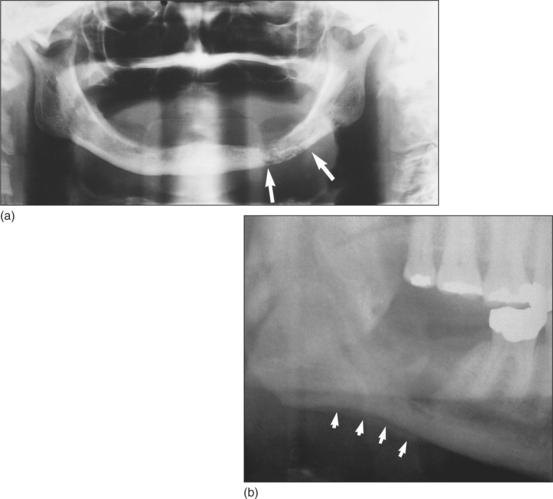

The clinical features are thus those of infection in general, plus tenderness of more teeth than would be expected, possibly mobility of teeth, loss of function of the inferior alveolar nerve and numbness of the lower lip. Because of periosteal inflammation and stripping there is a firm or woody expansion of the affected bone area, with no clearly defined junction between the swelling and normal bone. The overlying skin may be mobile, provided there is little acute infection. If the infection is not rapidly resolved, bone resorption becomes evident on radiographs (Fig. 7.14a), necrotic bone may separate as a sequestrum, and new bone may form on the inner aspect of the stripped periosteum and may become visible on tangential radiographs (Fig. 7.14b). Eventually the weakened mandible may fracture.

image

Fig. 7.14 (a) Typical radiological appearance of osteomyelitis. Patchy bone resorption is highlighted by arrows. (b) A thin layer of subperiosteal bone (arrows) has formed at the lower border of the mandible in a patient with osteomyelitis.